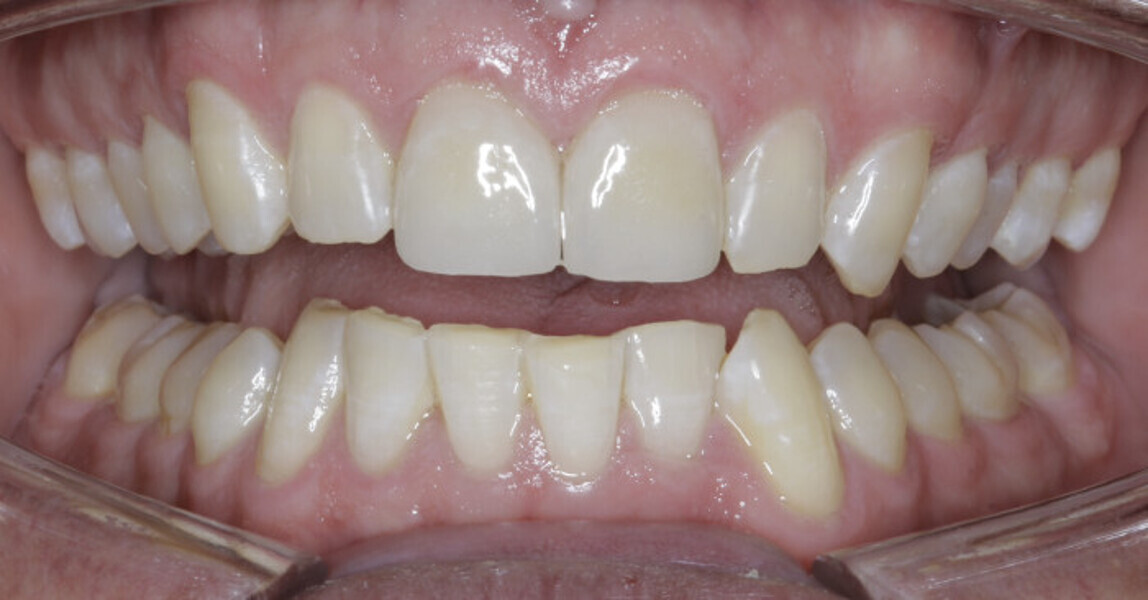

New Age orthodontics and orthopaedics with temporary anchorage devices